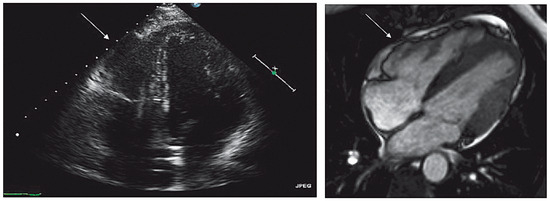

Case report. A 63-year-old hypertensive male presented with atypical chest discomfort and breathlessness on exertion [...]